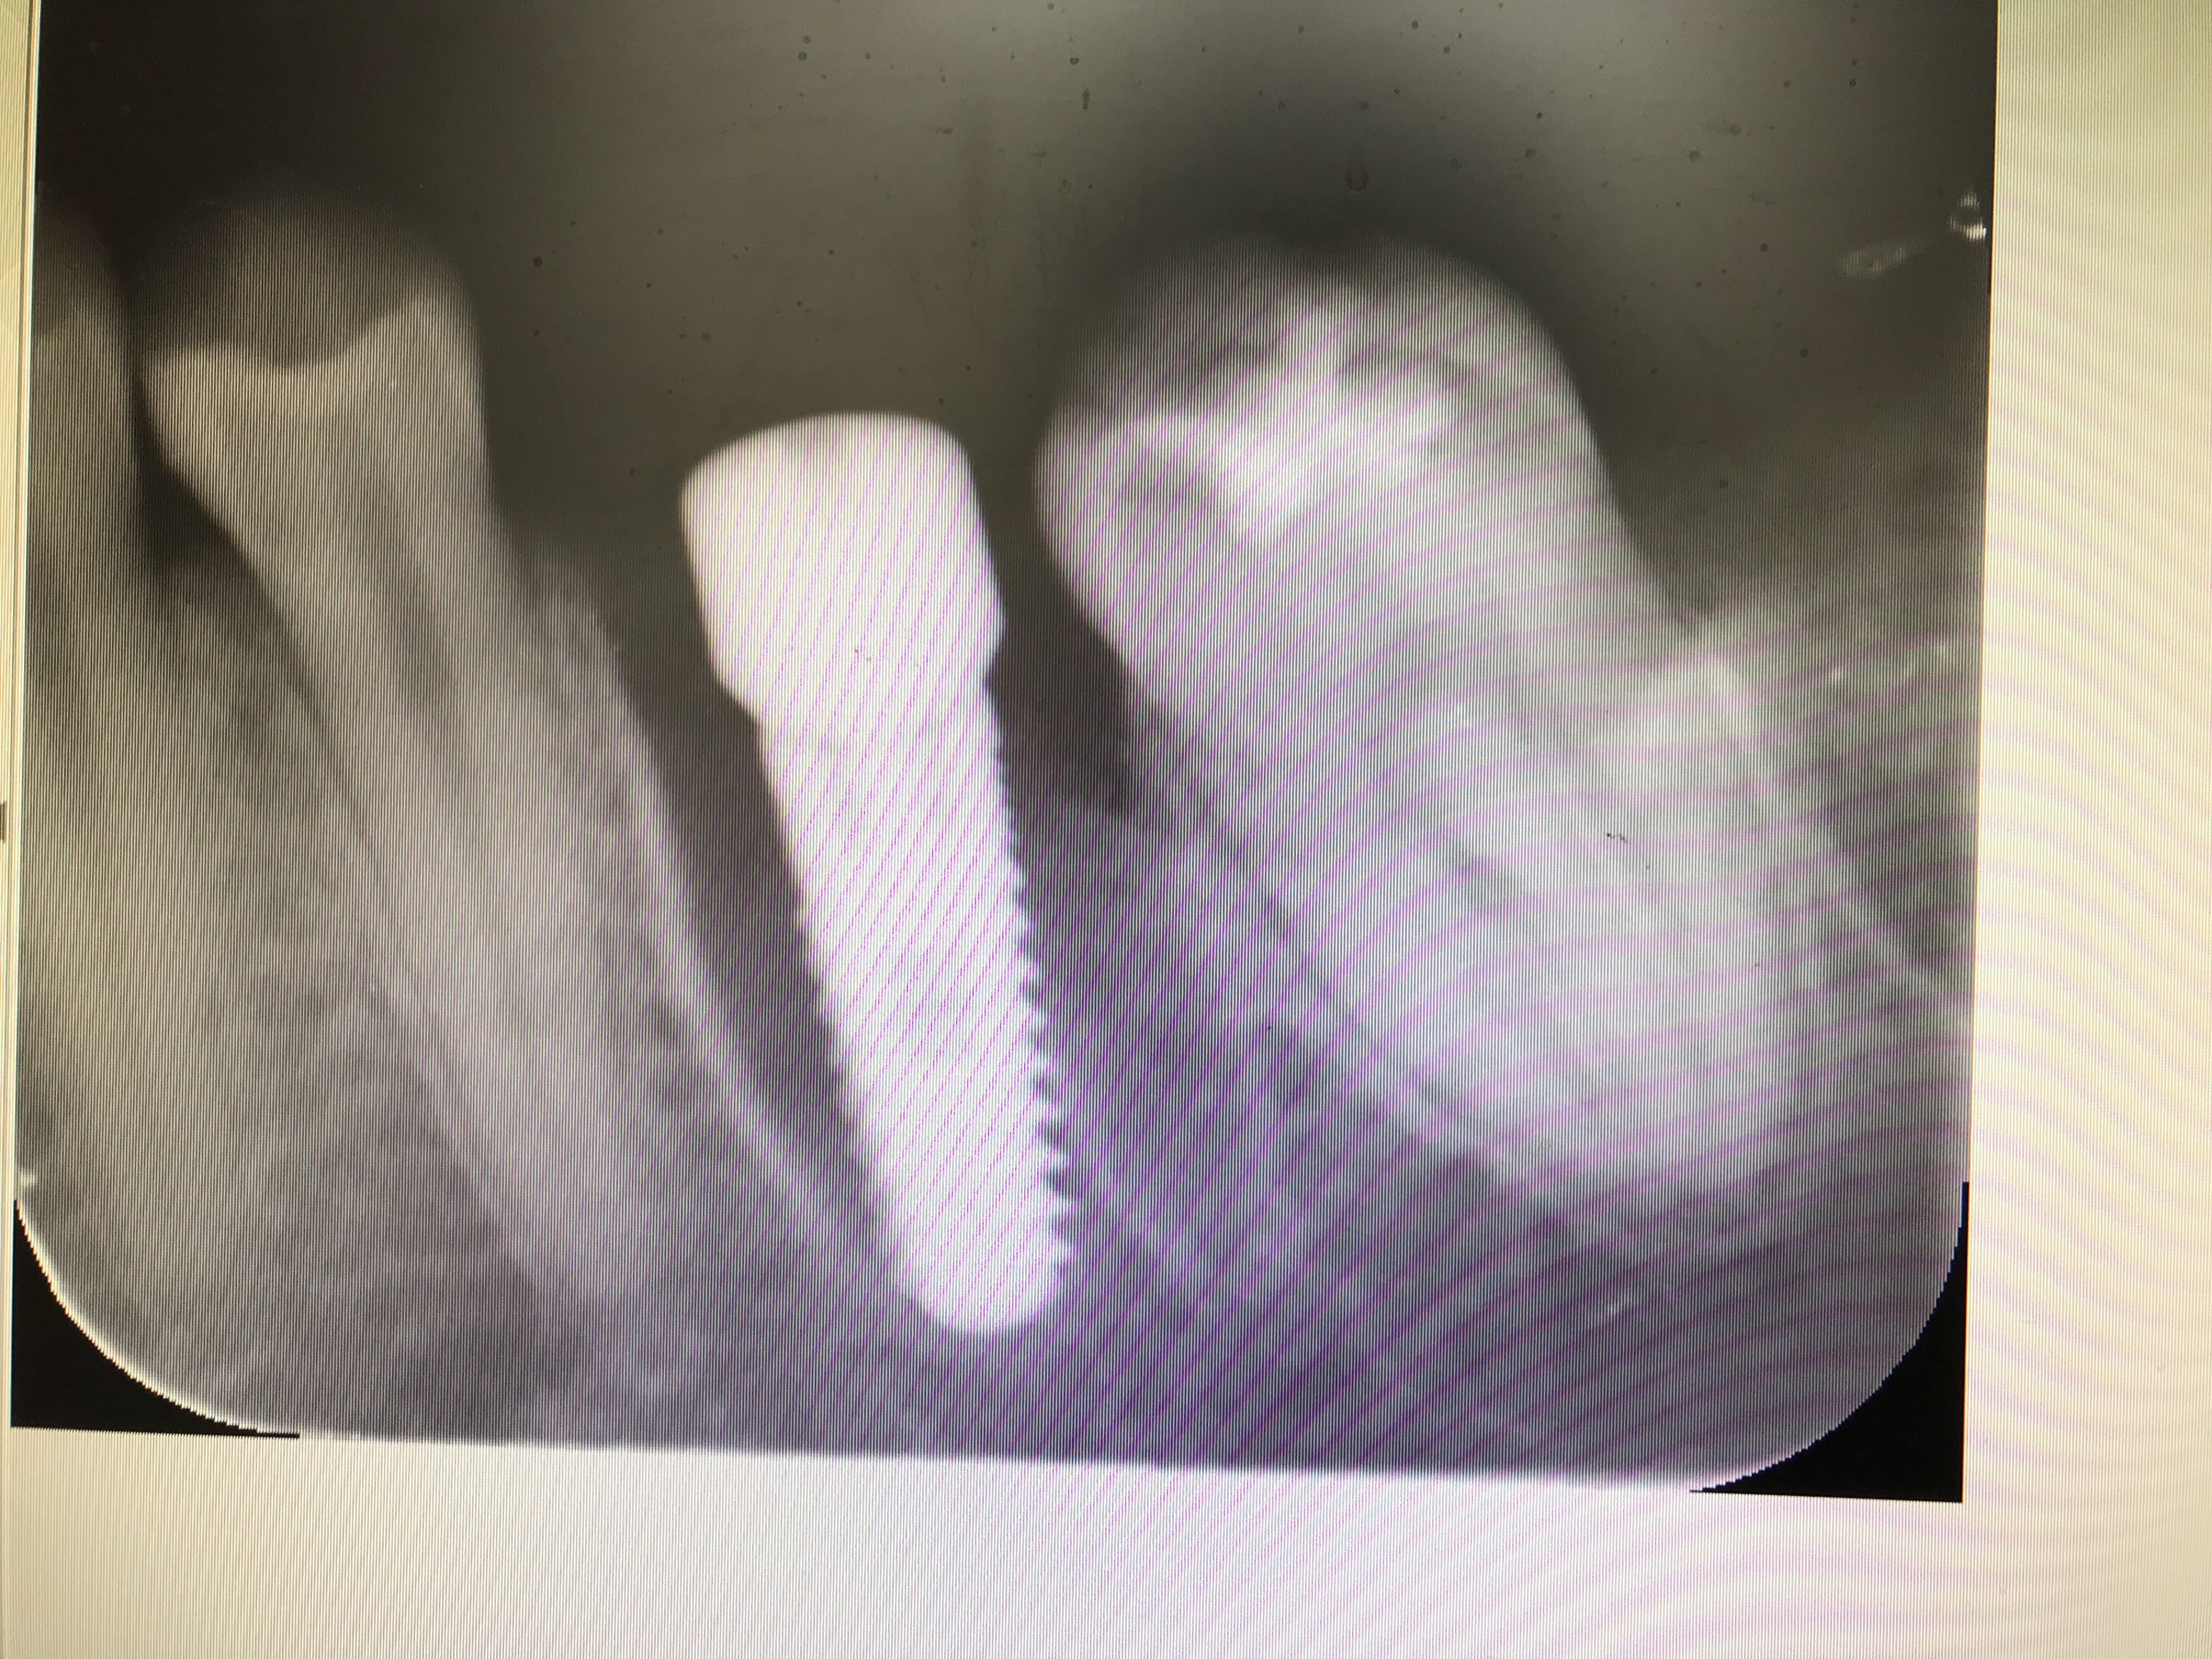

Bin moi pour coller l'IC je fais une ERI, en moins de 15 min cela va de soi, avec un matériau que la gencive elle aime bien en implanto et hop une dent de sauvée.

En plus les racines semblent propice à une extraction réimplantation.